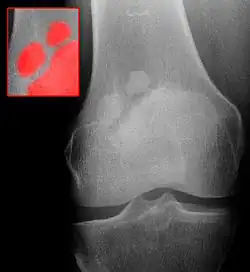

Die Patella partita (lateinisch patella = Schüssel, Teller; partiri = teilen) ist eine Störung der Ossifikation der Kniescheibe ohne eigentlichen Krankheitswert.

Die Kniescheibe ist zunächst knorpelig angelegt und bildet sich aus mehreren Knochenkernen (Ossifikation), die im Laufe des Wachstums verschmelzen. Bleibt diese aus, entsteht eine im Röntgenbild sichtbare scheinbare Teilung der Kniescheibe in zwei (Patella bipartita), drei (Patella tripartita) oder mehrere (Patella multipartita) Anteile. Die umgebende knorpelige Anlage ist nicht geteilt.

Die Diagnose wird im Röntgenbild gestellt. Die unverbundenen Anteile finden sich meist im oberen/seitlichen Rand der Kniescheibe.